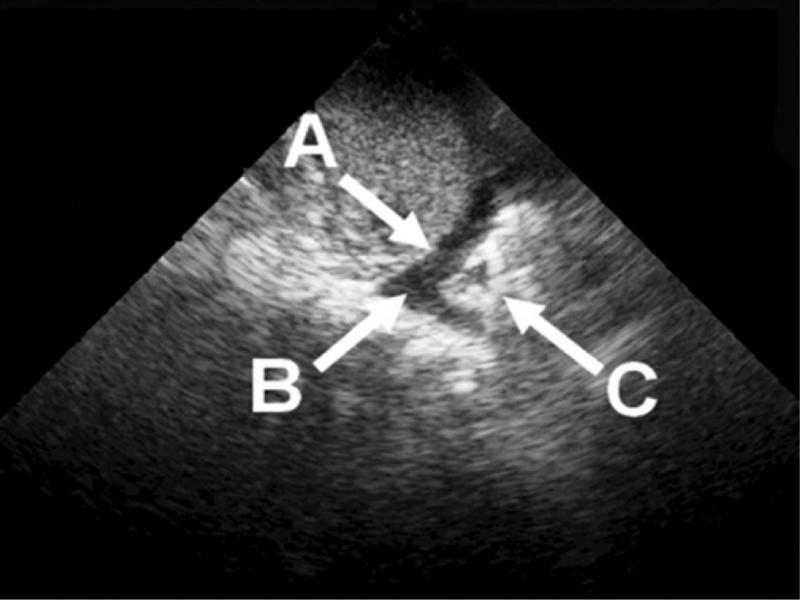

Fig. 2.

An ultrasound image of: A – diaphragm; B – pleural fluid (with fluid layer thickness measurement); C – pulmonary parenchyma within the pulmonary tissue